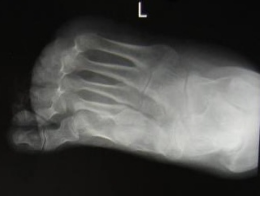

先天性马蹄内翻足

手足短骨解剖及常见疾病的影像学表现